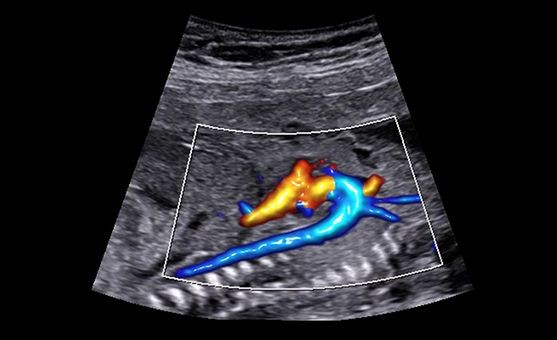

- BAREVNÝ A ENERGETICKÝ DOPPLER

SAMSUNG HERA W9

Seznamte se s novým prémiovým ultrazvukem navrženým ke zvýšení důvěry a efektivity ve zdravotní péči pro ženy. Nový ultrazvukový systém HERA W9 kombinuje špičkovou zobrazovací technologii s ergonomickým designem pro pokrok v pracovním toku. Díky inovativní technologii Crystal Architecture ™ a špičkovým technologiím zpracování obrazu vytváří HERA W9 realistické obrázky ve vysokém rozlišení pro výjimečnou přesnost.